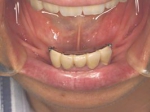

術前術前主訴-バネの目立たない入れ歯にしたい 装着前 義歯の内面義歯の内面義歯の内面(内側に赤いプラスチックが見えますがこれが消耗品で半年に一度くらい交換すれば元の維持が復活します。) 義歯装着後義歯装着後義歯装着後 バネが無いので入れ歯を使っているのが、外からはわからないくらいです。 義歯装着時正面像義歯装着時正面像義歯装着時正面像